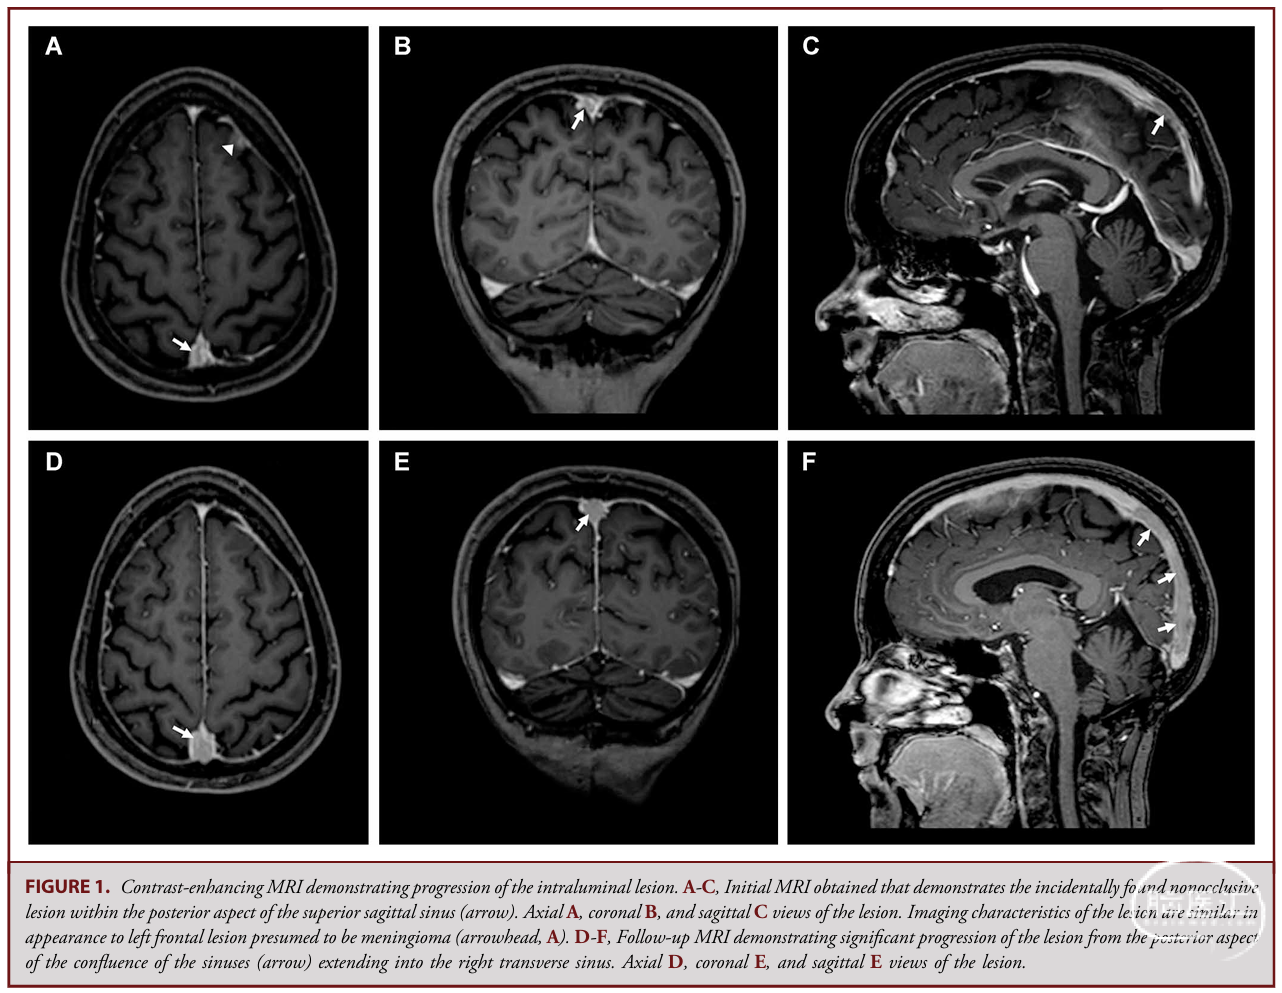

● 本例病变位于上矢状窦远端至右横窦,抗凝治疗后仍持续增大。

✔ 病变初始大小:2.2cm(类似其他脑膜瘤表现);3个月后:增长至5.5cm;抗凝治疗4个月后:仍持续进展并延伸至右横窦。